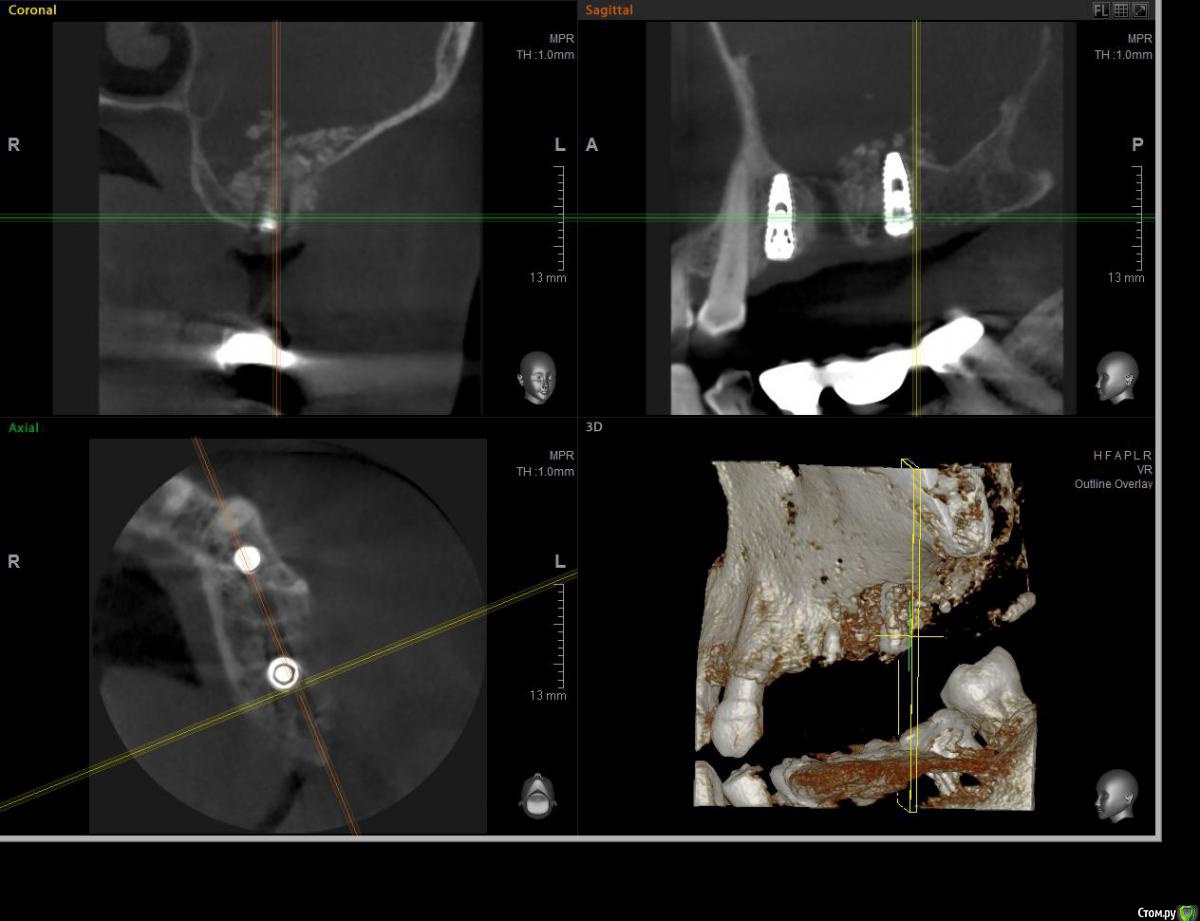

ossa-rr Опубликовано 12 июня, 2017 Поделиться Опубликовано 12 июня, 2017 (изменено) Коллеги, прошу помощи! В конце апреля установил два импланта 24 и 26. В области 26 с открытым синусом. Операция без осложнений, без перфорации и пр. Снял швы через 10 дней. Через месяц пациентка позвонила, сказала, что припухла. Явилась с клиникой периостита в области окна. Вскрыл , установил дренаж на сутки. Есть ли надежда или открывать и убирать все? И еще вопрос по перфорации на кт - как считаете, могла ли она возникнуть как следствие гнойного расплавления или все-таки непосредственно при синус - лифте?Скрины повторного кт : Изменено 12 июня, 2017 пользователем ossa-rr Ссылка на комментарий

kamranchick Опубликовано 12 июня, 2017 Поделиться Опубликовано 12 июня, 2017 Коллеги, прошу помощи! В конце апреля установил два импланта 24 и 26. В области 26 с открытым синусом. Операция без осложнений, без перфорации и пр. Снял швы через 10 дней. Через месяц пациентка позвонила, сказала, что припухла. Явилась с клиникой периостита в области окна. Вскрыл , установил дренаж на сутки. Есть ли надежда или открывать и убирать все? И еще вопрос по перфорации на кт - как считаете, могла ли она возникнуть как следствие гнойного расплавления или все-таки непосредственно при синус - лифте?Скрины повторного кт :походу перфорация есть, понаблюдайте, думаю весь графт может инфицироваться тут и нужны снимки до Ссылка на комментарий

ПалСаныч Опубликовано 13 июня, 2017 Автор Поделиться Опубликовано 13 июня, 2017 по моему мнению перфорация есть, ибо графт разлетелся по пазухе. Думаю нужно все убрать из места подсадки, пазуху пропунктировать пару раз у ЛОРа, антибиотики, сосудосуживающие. И через месяца 2 контроль КЛТ. Ссылка на комментарий